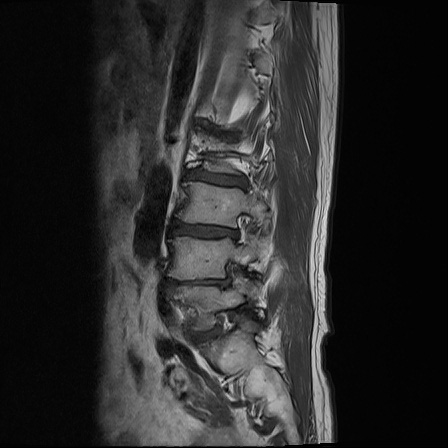

Ӵϲ ɿ ô ô 㸮 ٸ ̾ϴ. ϵ Ͻð ܻ 㸮 20⵿ ͽϴ. mri ˻ ɿ Ȳ ʹ ؼ Ȳ̶ ߽ϴ. ϻȰ ϰ 鼭 ½ϴ. ̴ ø鼭 Ͻô Ȳ ̷ ġ ص ȸ ϴ. δ Ҵµ, ù ȸԲ ˷ֽ ϰ β ϰ, ˷ֽ ü ƮĪ ϸ鼭 ȭǸ鼭 Ӵϲ ȸų ְ ǰ, β 鼭 ʴ β ؾϴ ŷο 1ϸ ijħ ڸ ǥ Ʈ ߽ϴ. ȸ ȭϽø鼭 Ϸ簡 ٸ ȸǽð 4ְ Ǿ Ǯ鼭 ¦ ҽϴ. ħ ȸ ȭϸ鼭 ڼ ü ƮĪ ϴ. ȥڼ Ͻʴϴ. ٳø鼭 ó Ͻ ʴϴ. ̾ ְ ̳ ߵ ʰ ϴ ȸԲ Ͻʴϴ. ʹ ϸ鼭 ϴ. Ȩ - ϱ ٴ Ȳ MRIԴϴ. |